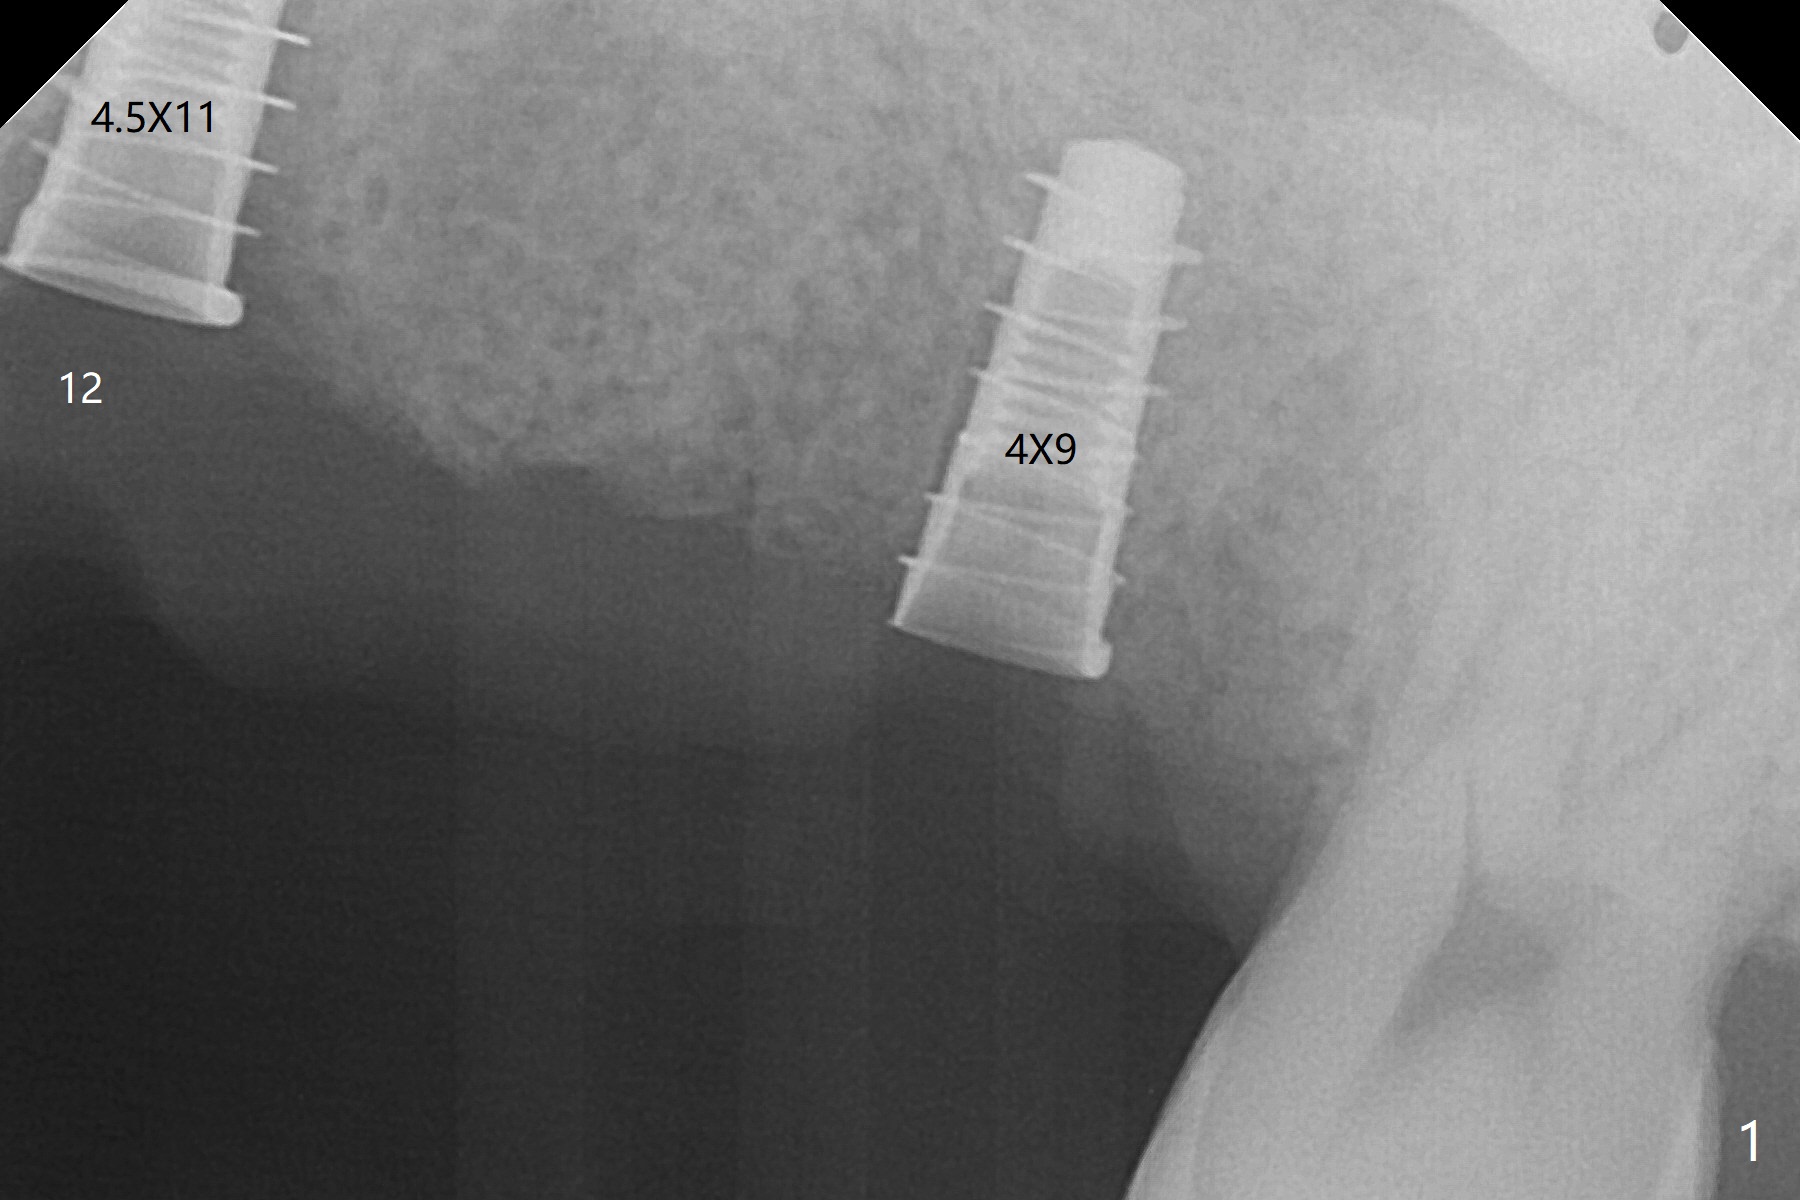

Immediate placement at #12 is smooth with 20 Ncm, whereas delayed one at #14 involves sinus membrane perforation; after insertion of PRF and mixture of autogenous bone and allograft, a shorter dummy implant tries in with stability (Fig.1). The final implant at #14 has ~60 Ncm, but the coronal palatal bone may be insuficient (Fig.2). Sticky bone is placed to bury the implant at #14 (Fig.3 *). After placement (incomplete, Fig.3 <) of a 4.5x7.5(4) mm pair abutment, setting acrylic is applied around the abutment, over the bone graft at #14 (to prevent loss) and pressed into the undercuts of the proximal surfaces of the neighboring teeth for retention (Fig.4). The sockets at #12 heals 8 days postop when a 2nd acrylic dressing dislodges (Fig.5). It appears that the retention of 3-unit acrylic dressing is poor. The wound at #14 also heals, but it would be better to make an incision to save the soft tissue (Fig.6). The bone/implant gap reduces at #13 five months postop (Fig.7 (complete abutment seating)). There is no implant thread exposure at #13 (immediate), while minor exposure mesial to #15 (delayed). The patient complains of food impaction between #13 and 14 buccally 6 months post cementation (Fig.8). Return to Upper Molar Immediate Implant, No Deviation 19 Next Case Xin Wei, DDS, PhD, MS 1st edition 01/21/2020, last revision 02/03/2021